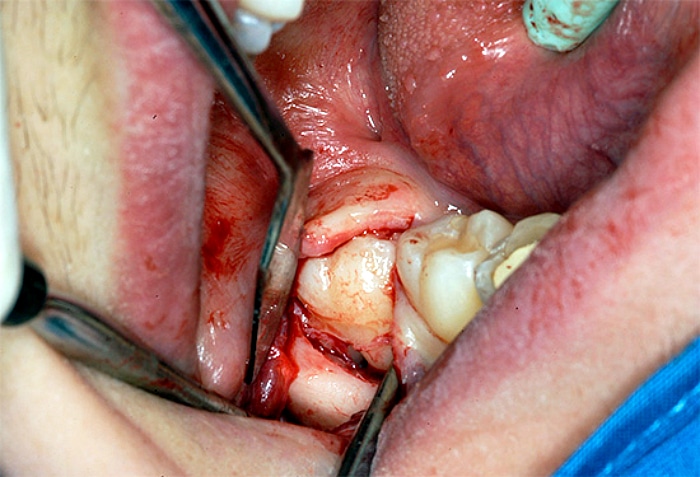

Если зуб мудрости никак не может прорезаться, а боль и отечность десны не исчезают, а только усиливаются, нужно обратиться к врачу. Стоматолог сделает на десне надрез и освободит зуб. Эта операция проводится под местным наркозом и не занимает много времени.

Метод иссечения десневого капюшона проводится для того чтобы помочь зубу мудрости прорезаться.